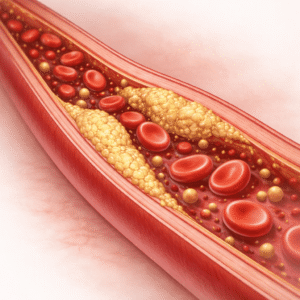

Controlul colesterolului

Ce este Controlul Colesterolului? Colesterolul este o substanță asemănătoare grăsimilor…

Află mai multe

Controlul colesterolului simplificat: Modalități susținute de știință pentru a îmbunătăți nivelul colesterolului

Când vine vorba de protejarea inimii și sănătății tale, controlul colesterolului joacă…

Citește articolul

Controlul colesterolului: Alimente, obiceiuri și sănătatea inimii

Colesterolul ridicat este un factor major de risc pentru bolile de inimă,…

Citește articolul

Controlul colesterolului: Alimente, obiceiuri și sănătatea inimii

Începe chestionarul